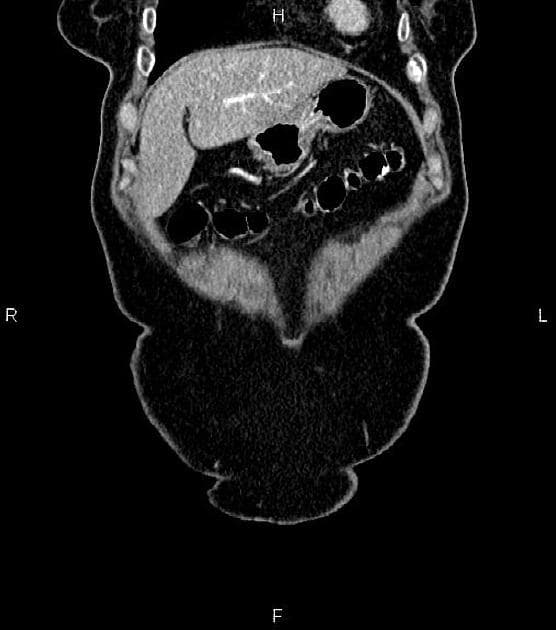

Ca bệnhU sarcoid ở tụy

U sarcoid ở tụy (pancreatic sarcoidosis)

U sarcoid ở tụy là một biểu hiện hiếm gặp của bệnh sarcoidosis toàn thân, xảy ra ở dưới 1% các trường hợp. Bệnh thường biểu hiện dưới dạng xâm nhiễm nốt lan tỏa hoặc khối khu trú, phổ biến nhất ở đầu tụy, dễ nhầm với ung thư biểu mô ống tụy. Các hình ảnh học như khối tụy giảm tỷ trọng kèm giãn nhẹ ống chính rất khó phân biệt với ác tính. Tuy nhiên, sự vắng mặt của xâm lấn mạch máu hay di căn xa, kết hợp với các tổn thương ngoài tụy đặc trưng—như phì đại hạch rốn phổi hai bên và các nốt phổi ngoại vi—là dấu hiệu nghi ngờ mạnh đến một quá trình u hạt. Xác định chẩn đoán thường cần sinh thiết mô học, nhưng sự phối hợp lâm sàng và hình ảnh học có thể hỗ trợ chẩn đoán khi có tổn thương hệ thống rõ ràng. Điều trị chủ yếu mang tính bảo tồn bằng corticosteroid, trái ngược với can thiệp phẫu thuật trong ung thư tụy.